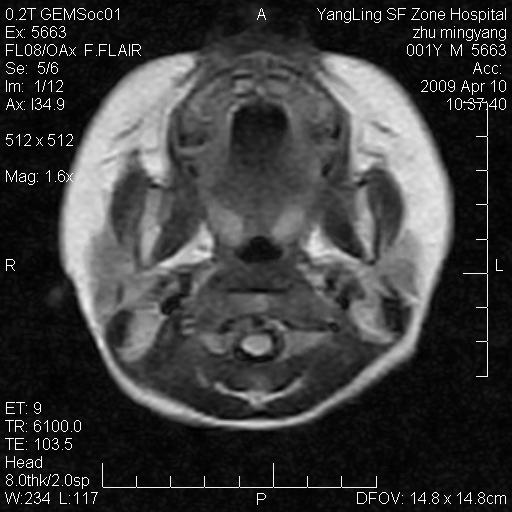

患者:1岁半,两天前外伤收住我院,ct检查小脑占位

考虑星形细胞瘤,建议增强

髓母细胞瘤或血管母细胞瘤,增强后可以鉴别;影像资料见 <。鱼博浪老师的《中枢神经系统ct与mr鉴别诊断》 小脑部肿瘤章节。

髓母细胞瘤或血管母细胞瘤!支持!

支持考虑髓母细胞瘤

考虑----髓母细胞瘤可能性大

考虑髓母细胞瘤或室管膜瘤。

支持髓母细胞瘤。

考虑髓母细胞瘤。

考虑髓母细胞瘤或星形细胞瘤

考虑髓母细胞瘤.

考虑髓母细胞瘤可能性大。

小脑肿瘤.考虑髓母细胞瘤可能.

就病灶部位及临床资料首先考虑髓母.